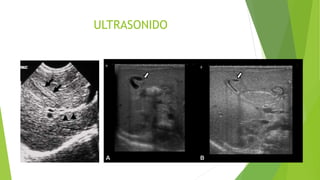

ULTRASONIDO

ammagrafía hepatobiliar)